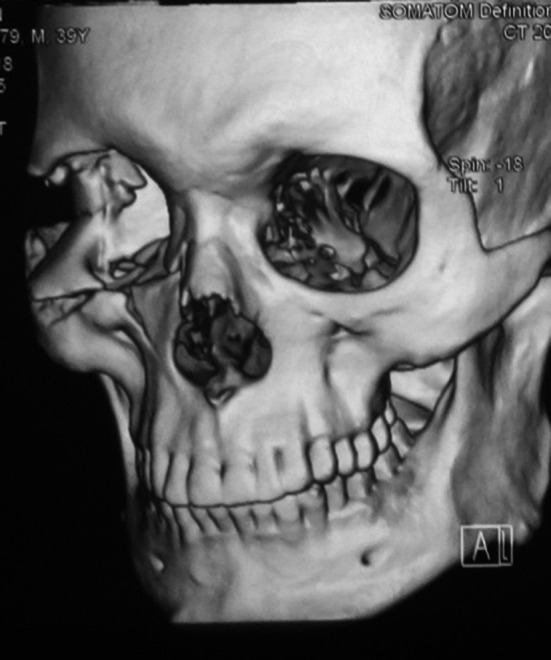

Any linear fracture which involved one or more than one processes of zygomaticomaxillary complex without any deviations was included in conventional group (Fig. 1).

Fig. 1.

Conventional fracture